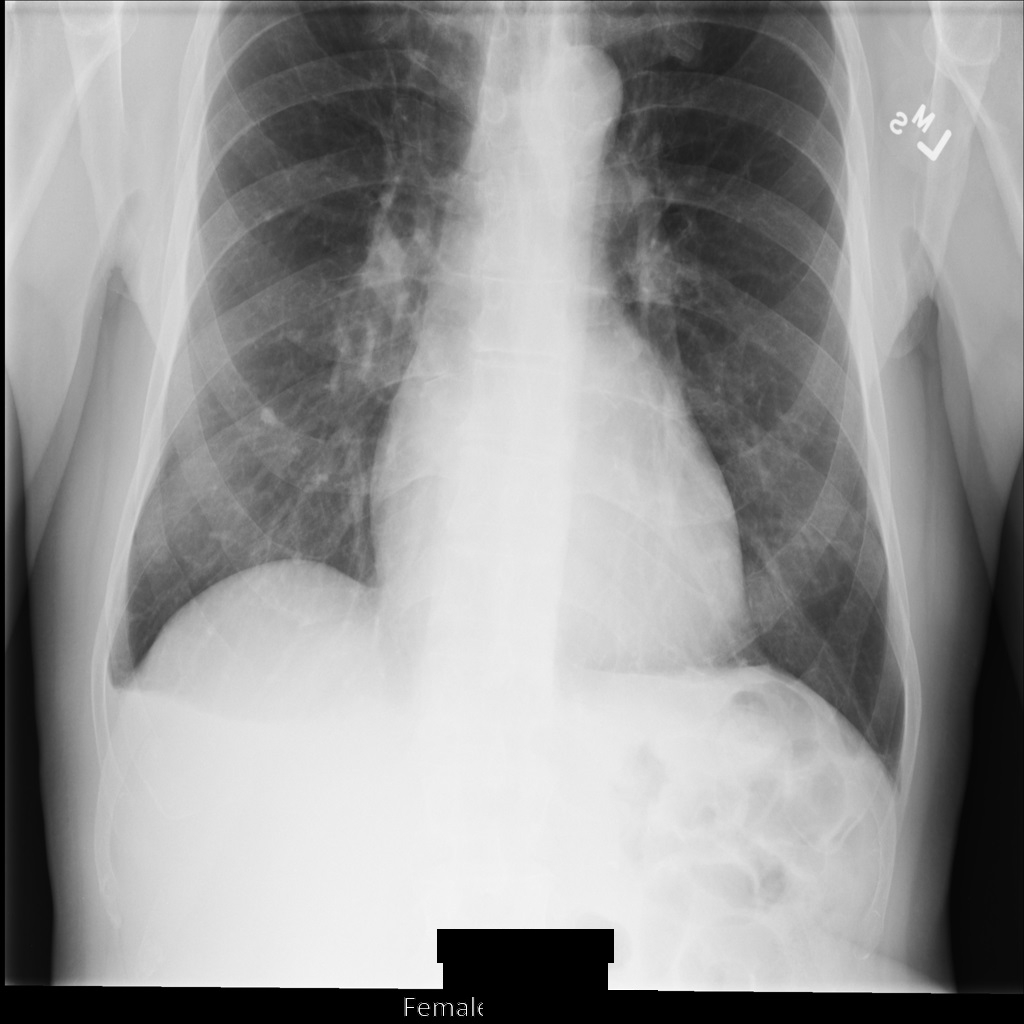

Sample image

Some samples in this page contain an output of the de-identified image. Each sample uses the following original image as its input. You can compare the output image from each de-identification operation to this original image to see the effects of the operation:

xray_original

After de-identifying the image using REDACT_ALL_TEXT, the image looks like this. Notice that all the burned-in text at the bottom of the image has been redacted.

Figure 1. The DICOM instance after de-identification using REDACT_ALL_TEXT.